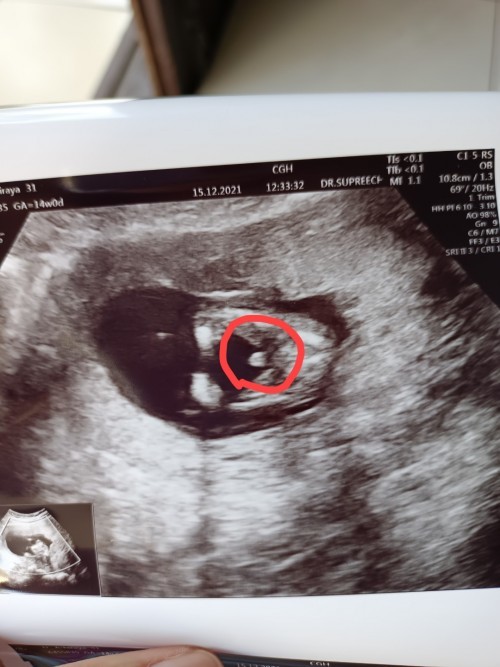

14 w ค่ะ บ้านนี้

14w จ้า